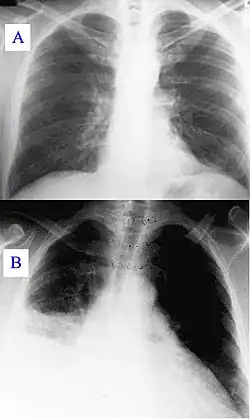

During its course, the disease can progress to an atypical pneumonia, which can result in a life-threatening acute respiratory distress syndrome, whereby such symptoms usually occur during the first four to five days of infection.[6]

Q fever can cause endocarditis (infection of the heart valves) which may require transoesophageal echocardiography to diagnose. Q fever hepatitis manifests as an elevation of alanine transaminase and aspartate transaminase, but a definitive diagnosis is only possible on liver biopsy, which shows the characteristic fibrin ring granulomas.[21]